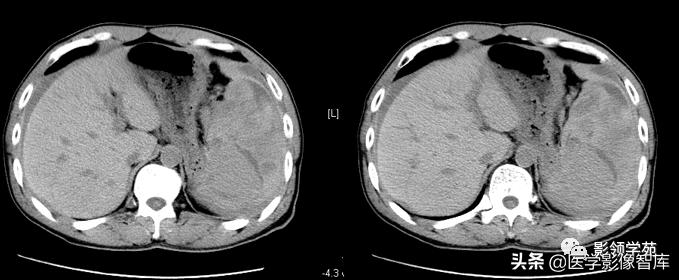

CT平扫:

1)脾脓肿早期表现为脾弥漫性肿大,密度稍低且均匀。

2)发生液化坏死后,见圆形或椭圆形低密度区,CT值大多在20HU左右,边界不清。

3)少数脓肿内可见小气泡或气液平面为特征性表现。

增强扫描:见脓肿壁明显强化,中心坏死区无强化。当脓肿为多发而又较小时,则常表现为增强后脾内斑点状或粟粒状低密度灶。